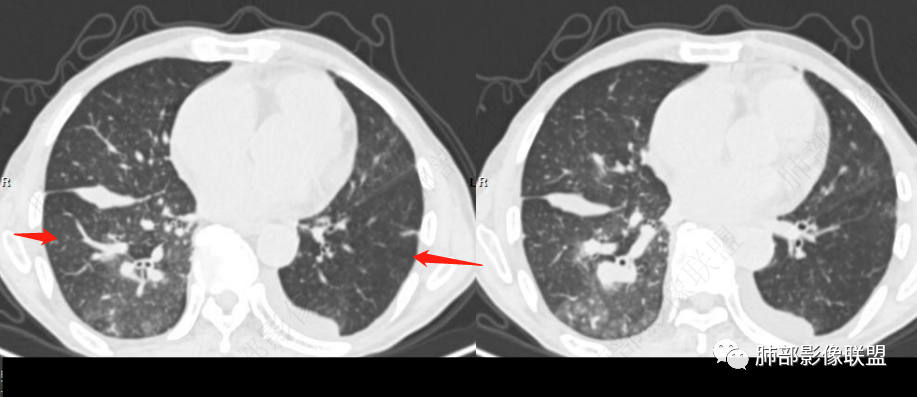

从肺动脉的主体分析:左肺动脉好像起始部就开始狭窄。

现在给的图像:是鼠尾状狭窄,而不会局部膨隆,远端细小那种。

右侧的肺动脉增粗肯定与代偿有关。

现在的问题是自左肺动脉狭窄的原因:是急性栓塞?炎性病变?慢性血栓?

3、右肺改变符合肺动脉高压导致

4、肺动脉改变:左肺动脉起始部突然狭窄(右肺动脉代偿增大——继发肺内改变)

南边:

就是根源还是与左肺动脉起始部狭窄相关性大。

无非:急性栓塞、慢性栓塞、炎症、肿瘤。

目前的依据,我觉得急性栓塞的特点不太明显啊。